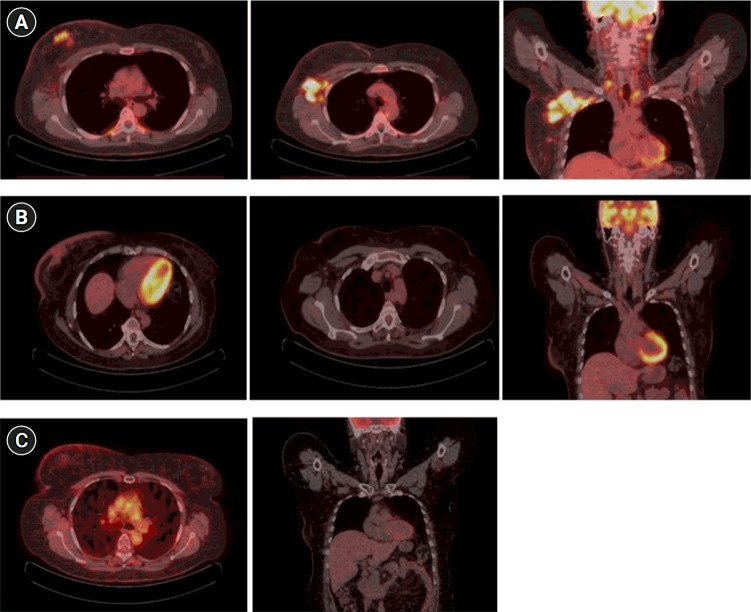

Inflammatory breast cancer (IBC) is a rare, aggressive form of breast cancer characterized by poor prognosis. The treatment requires a multidisciplinary approach, with neoadjuvant chemotherapy, surgery, and radiation therapy (RT). Particularly, high doses of conventional RT have been historically delivered in the adjuvant setting after chemotherapy and mastectomy or as radical treatment in patients ineligible for surgery. Here, we report the case of a 49-year-old woman patient with IBC unsuitable for surgery and treated with a combination of lattice RT and fractionated external beam RT concurrent with trastuzumab, with a curative aim. One year after RT, the patient showed a complete response and tolerable toxicities. This is the first reported case of a not-operable IBC patient treated with this particular kind of RT.